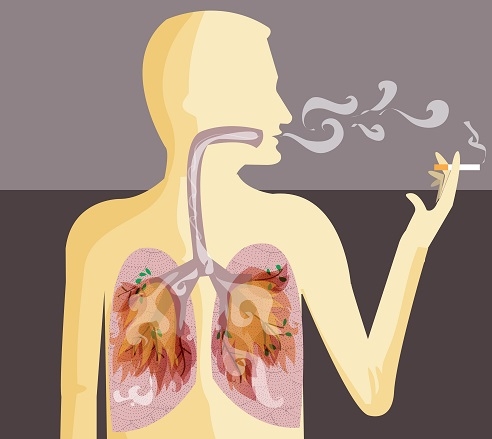

- 면역력이 약한 분, 만성 질환자, 65세 이상 노인, 유아는 폐렴 예방접종을 고려하세요.

- 폐렴 증상은 초기에 감기와 유사하지만, 증상이 오래가고 점점 심해지면 병원 방문 필수입니다.

- 조기 진단과 적절한 항생제 치료로 대부분 완치 가능하지만, 방치 시 합병증 위험이 큽니다.

폐렴은 단순한 감기와 달리

빠르게 진행되고 생명까지 위협할 수 있는 질환입니다.

특히 요즘처럼 날씨 변화가 심한 시기엔

초기 증상을 예민하게 감지하는 것이 무엇보다 중요하죠.오늘 알려드린 10가지 증상 중

하나라도 자주 반복되거나 오래 지속된다면

꼭 병원을 방문해 정확한 진단을 받아보세요.건강은 아무리 강조해도 지나치지 않으니까요 😊